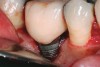

The results of these studies suggest that the shorter the prosthetic abutment height, the greater the amount of MBL that can be expected with bone-level implants (Figure 2). While these studies only measured MBL, it may be surmised that similar MBL patterns would develop on the facial and lingual aspects when the prosthetic abutment height is less than 2 mm. With greater MBL, the risk for bacterial colonization of the implant surface may increase. It would seem prudent, therefore, to place the crown margin in a position that would minimize MBL.

Fig 2. The height of this abutment was less than 2 mm on the facial. This may have led to additional marginal bone loss. Bacterial colonization of the abutment and the exposed implant body resulted in peri-implantitis.

Figure 2